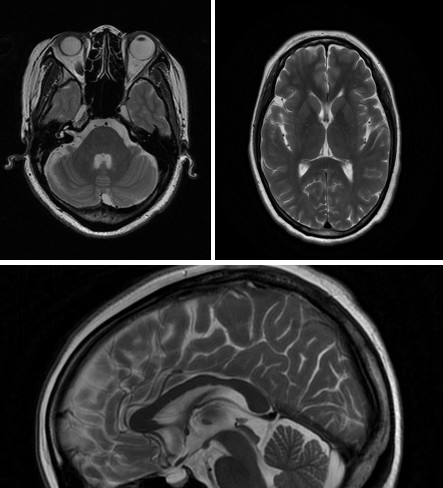

影像:MRI脑实质未见异常。